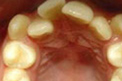

牙齿修复案例展示 TAIKANG BYBO DENTAL